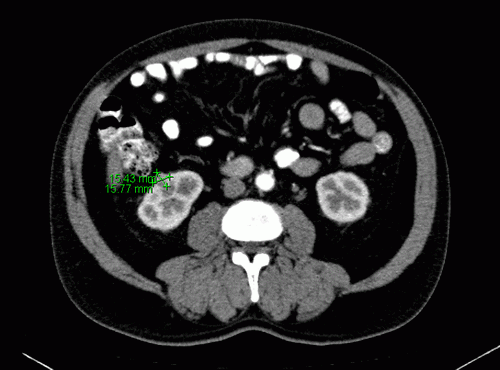

CT-Diagnostik

Am Unterpol der rechten Niere ventral Nachweis einer aktuell ca. 1,5 × 1,5 cm großen, früharteriell inhomogen KM-aufnehmenden Struktur, im zeitlichen Verlauf langsam größenprogredient, in der VU von 2006 noch nicht nachweisbar. Kein Anhalt für Filiae.